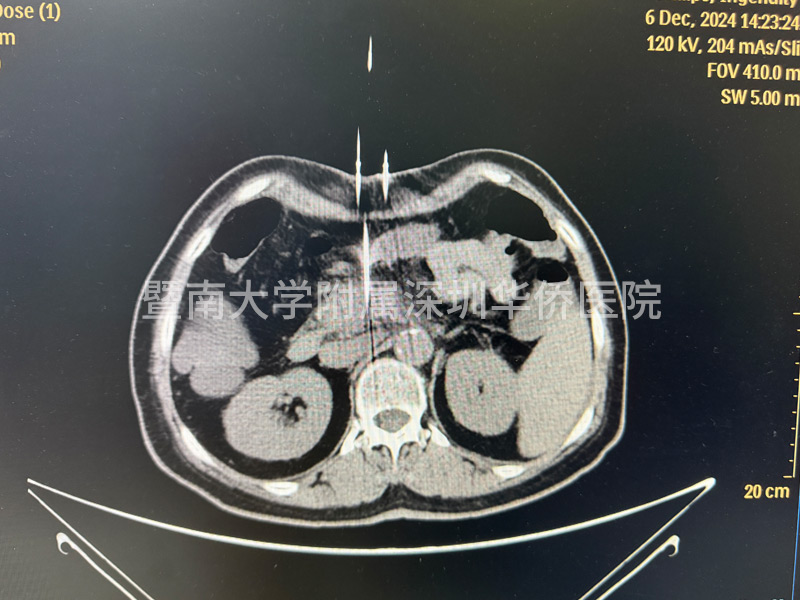

李女土的腫瘤在胰頭位置,大小為2.8*3釐米,已經包繞腸繫膜上動脈,失去了手術機會,在得知廣東省應用了國產奈米刀治療手術技術後,決定不遠千里來到深圳華僑醫院,接受奈米刀消融手術。

上午11點,李女士正式進入手術室,多位相關領域專家,透過國產研發的新型裝置正式對李女士進行手術,奈米刀消融技術適合中晚期的胰臟癌的治療,這臺手術裝置在產品設計中,具有全球領先的核心技術,實現了在消融過程中,電壓恰到好處,作用於細胞膜磷脂雙分子層,形成不可逆電穿孔,誘導細胞凋亡,啟用細胞免疫,經過幾個小時的奮戰,李女士成功完成手術治療,此次奈米刀消融手術,順利開展完成!

許林鋒教授介紹:“奈米刀消融技術對操作者要求較高,與我們傳統的消融手術也不同,以前的消融手術一個針就可以了,放到腫瘤的中心的部位,而奈米刀消融最少要有2根針,它是利用兩個電極針之間的放電,就是一個公分的距離,可能有2-3千伏電壓,所以說對電極針的定位非常重要。”

在超聲或CT引導下,奈米刀治療系統能夠精確計算出消融區域的形狀和體積,並告知探針的有效消融範圍。治療計劃精確到毫米級別,為患者提供個性化的治療方案。